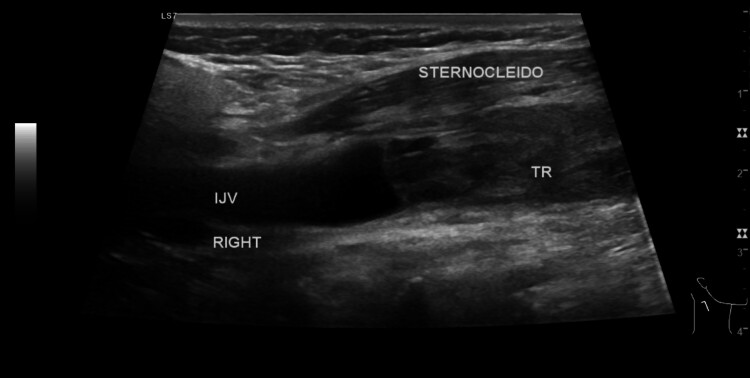

Lemierre's syndrome is marked by presence of septic thrombophlebitis in the internal jugular vein. This case report describes a 57-year-old woman who presented with a progressively swelling neck with onset 1 day prior to admission. She had a history of untreated dental infection. Physical examination revealed slightly increased blood pressure, at 140/80 mmHg, and a painful, erythematous, warm swelling in the mid area of the neck. Ultrasound of the neck revealed occlusive intraluminal thrombus in the right internal jugular vein, a computed tomography (CT) scan with contrast showed that there was a blockage in the right jugular vein. The mainstay treatment for Lemierre's syndrome is antibiotics, while administration of anticoagulants remains controversial. The patient was treated conservatively, with administration of antibiotics and anticoagulant. Several days later the patient's condition had improved significantly, with less pain and reduced swelling.

Abstract Image